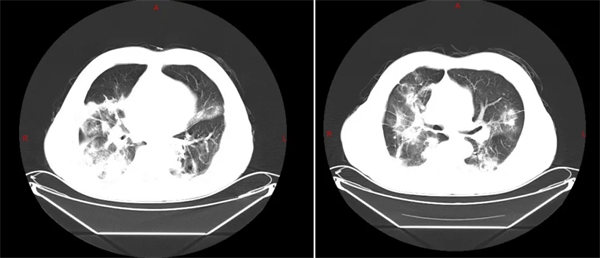

患者武某某因“多發(fā)性骨髓瘤”入住我院血液腫瘤科。入院前1月患者開始出現(xiàn)咳嗽、咳痰,發(fā)熱的等癥狀,血液科患者因其原發(fā)病導(dǎo)致自身免疫力低下,且長期服用激素,為高危易感人群,重癥肺炎是常見且兇險(xiǎn)的并發(fā)癥。然而,令人擔(dān)憂的是,依據(jù)細(xì)菌培養(yǎng)結(jié)果,抗感染治療后,患者的臨床癥狀與影像學(xué)檢查均未見明顯好轉(zhuǎn),感染指標(biāo)持續(xù)在高位徘徊。療效欠佳,提示著此次感染的病原體可能非比尋常。

面對這一困境,朱暉主任醫(yī)師迅速發(fā)起院內(nèi)多學(xué)科會(huì)診(MDT)。呼吸與危重癥醫(yī)學(xué)科、感染科、影像科、藥劑科及檢驗(yàn)科的專家們齊聚一堂,共同探討病情。專家們仔細(xì)分析了患者的病史、影像學(xué)特征及治療反應(yīng),一致認(rèn)為:這極可能是一例非典型病原體感染,但也不排除為多發(fā)性骨髓瘤肺部浸潤可能。建議盡快行肺穿刺活檢,明確病理及病原學(xué),才能走出治療困境。

方向既定,重任落在了檢驗(yàn)科及病理科的肩上。多學(xué)科會(huì)診后檢驗(yàn)科李海英科主任立即取血清標(biāo)本給患者進(jìn)行莢膜抗原檢測,針對肺穿刺活檢組織標(biāo)本,檢驗(yàn)科李海英主任高度重視,帶領(lǐng)團(tuán)隊(duì)不僅進(jìn)行了常規(guī)的細(xì)菌、真菌培養(yǎng),更針對可疑病原體進(jìn)行了隱球菌莢膜抗原檢測及墨汁染色鏡檢等一系列精準(zhǔn)的靶向檢查。最終,在檢驗(yàn)科同仁的“火眼金睛”下,病原體露出了它的真面目:新型隱球菌。病理科也排除了多發(fā)性骨髓瘤導(dǎo)致肺部浸潤。

隱球菌感染在多發(fā)性骨髓瘤等免疫缺陷患者體內(nèi),可能引發(fā)嚴(yán)重甚至致命的播散性感染。此前的常規(guī)抗細(xì)菌藥物對其無效,正是導(dǎo)致前期治療“欠佳”的根本原因。

病原體明確后,血液腫瘤科團(tuán)隊(duì)立即調(diào)整治療方案,停用之前的廣譜抗菌藥物,轉(zhuǎn)而啟用高效、精準(zhǔn)的氟康唑抗隱球菌治療?;颊呖人钥忍得黠@改善,體溫正常,感染指標(biāo)也隨之下降,病情終于迎來了決定性的轉(zhuǎn)機(jī)。